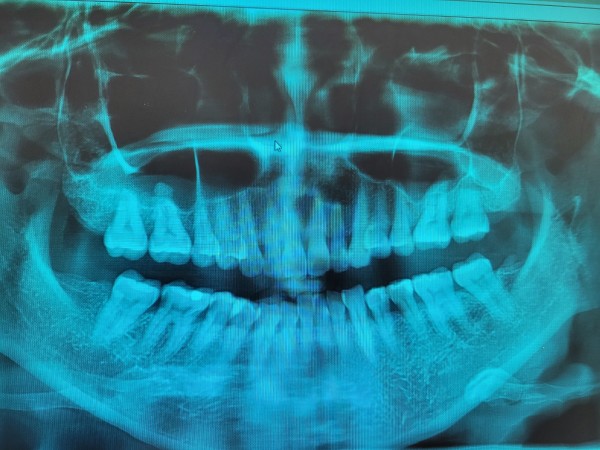

타 병원에서 엑스레이상에 체크된 아래 어금니 세개와

윗 이 한개 치료가 필요하다고 들었는데요..

아래 어금니 세개와 윗 이 한개 이렇게 4개 치아 모두 치료를 받아야 하는 상황인건지 궁금하구요.

치료를 할 경우 아래쪽 끝에서 두번째 어금니는 엑스레이상으로 봤을때 신경치료가 꼭 필요한 상황인지 궁금합니다.